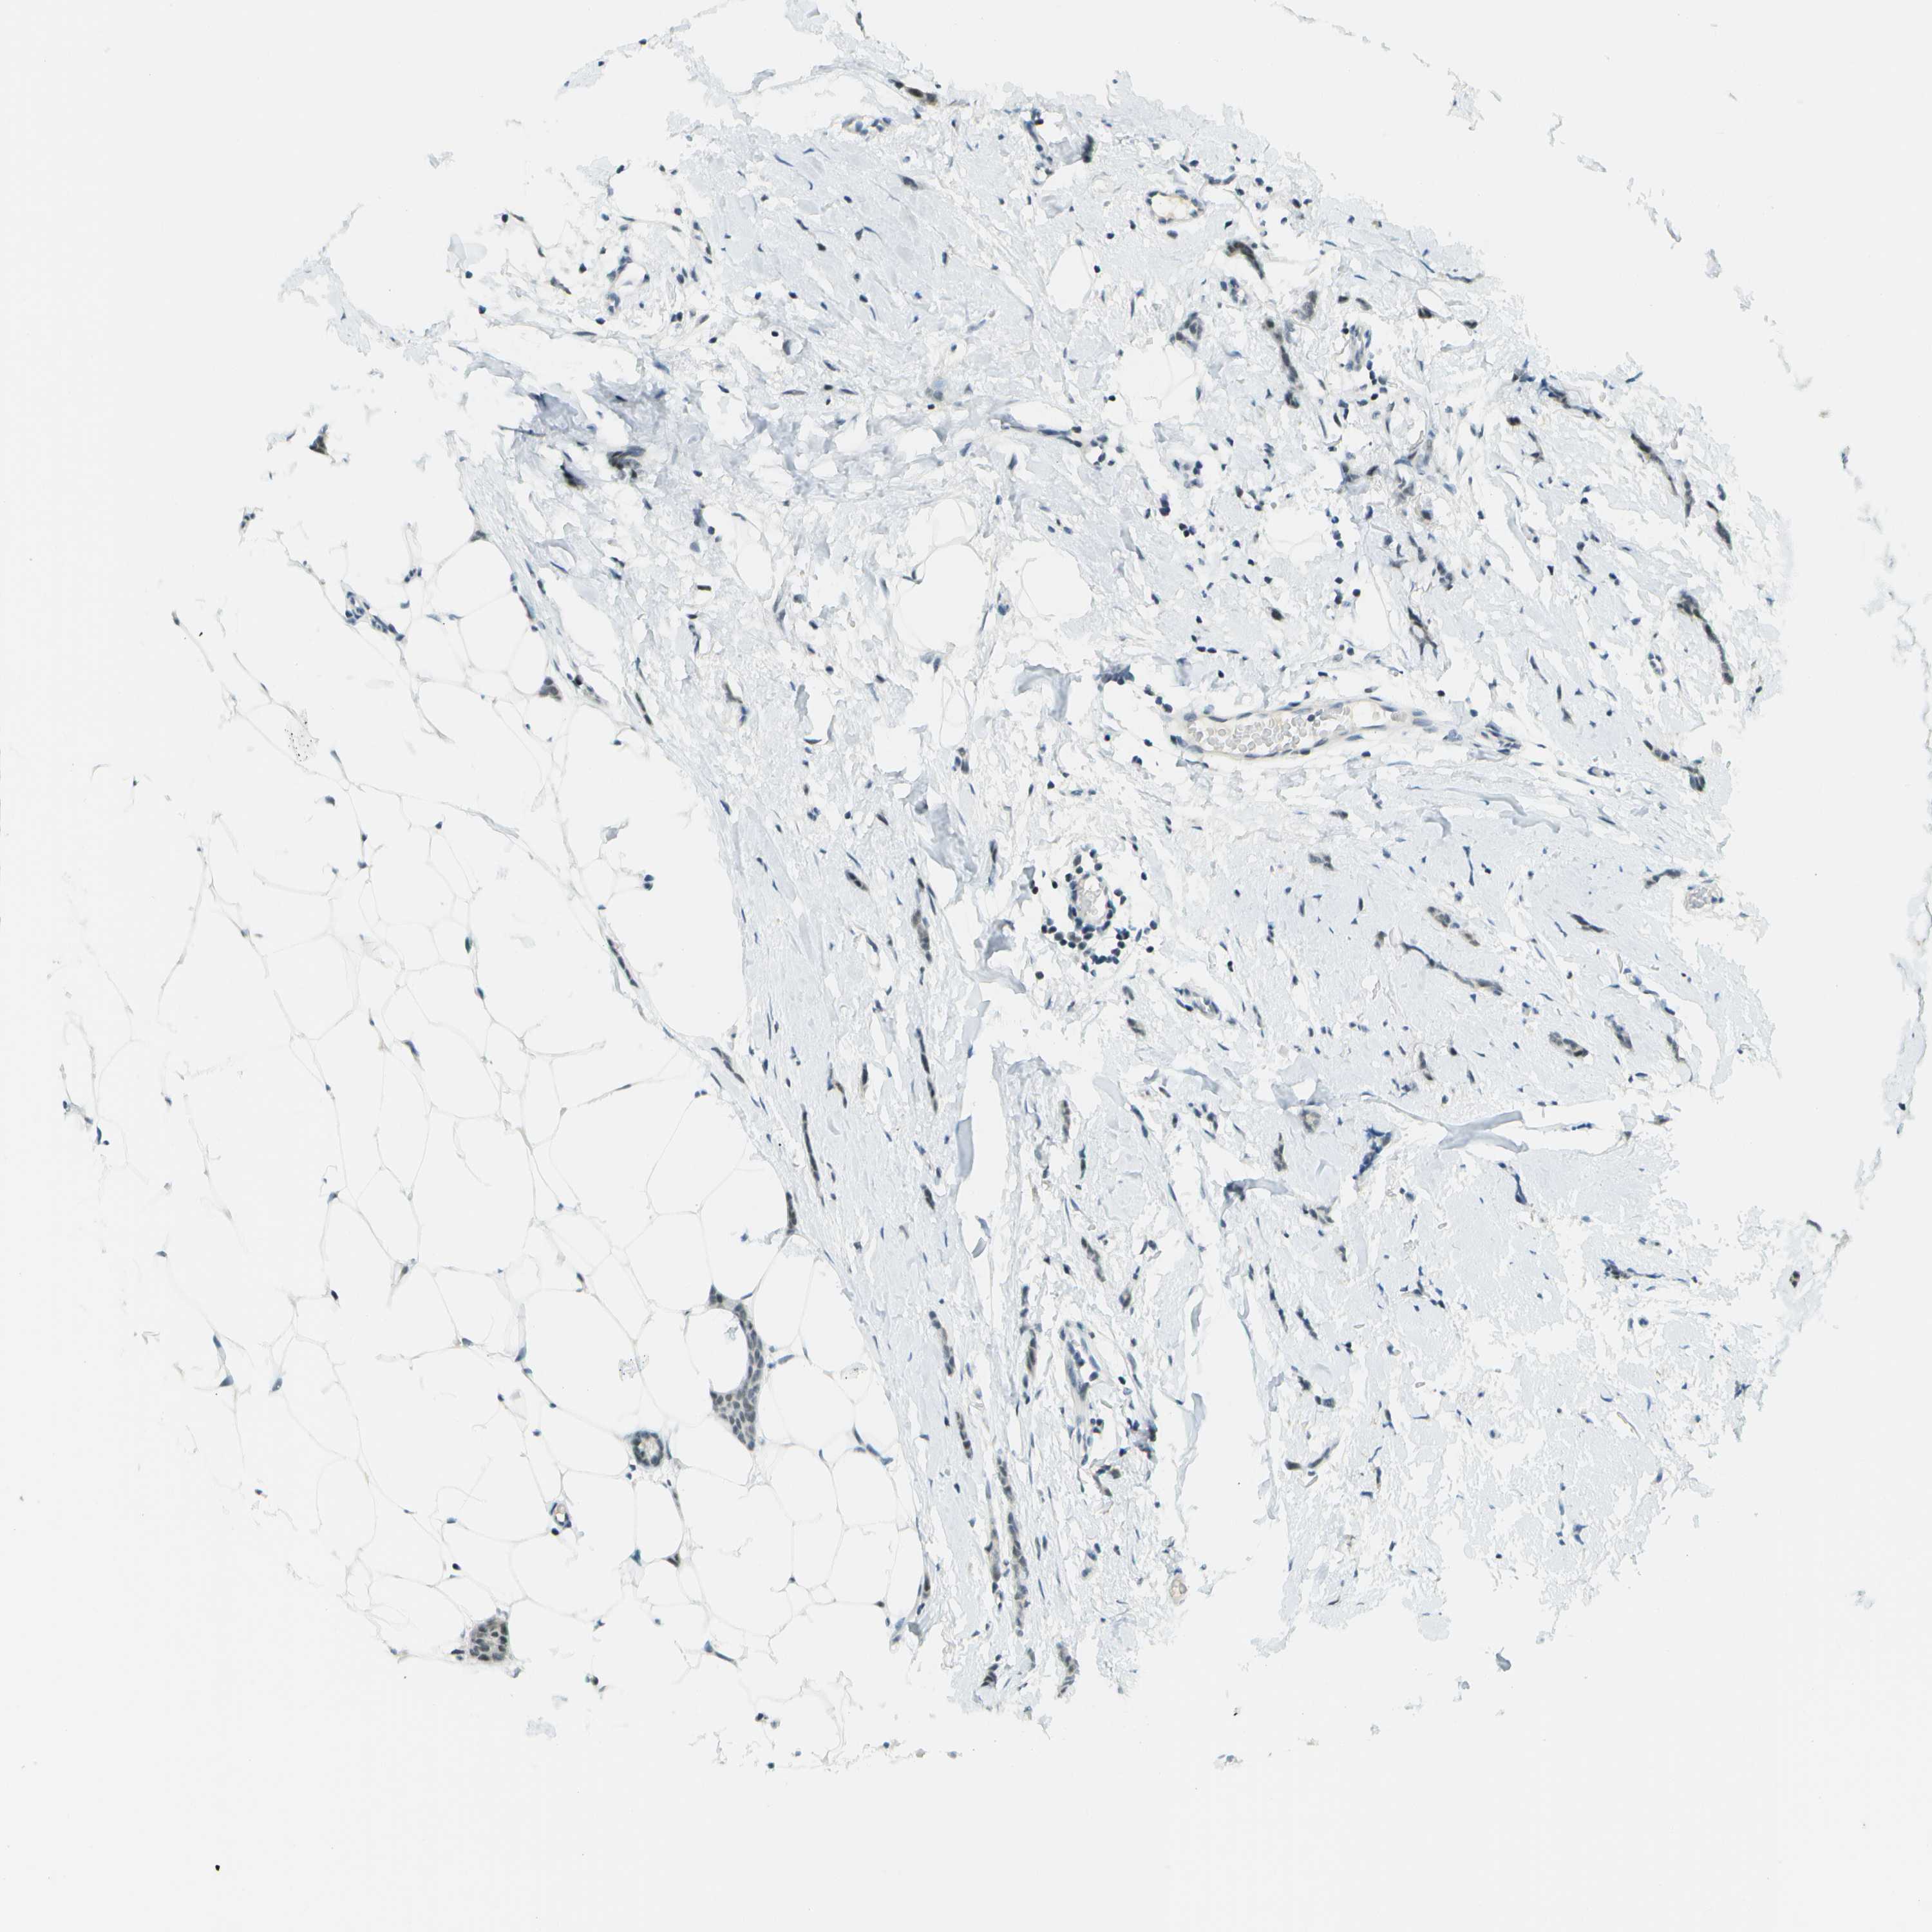

CANCER BREAST CANCER Show tissue menu

BRCA TCGA BRCA VALIDATION PROTEIN EXPRESSION